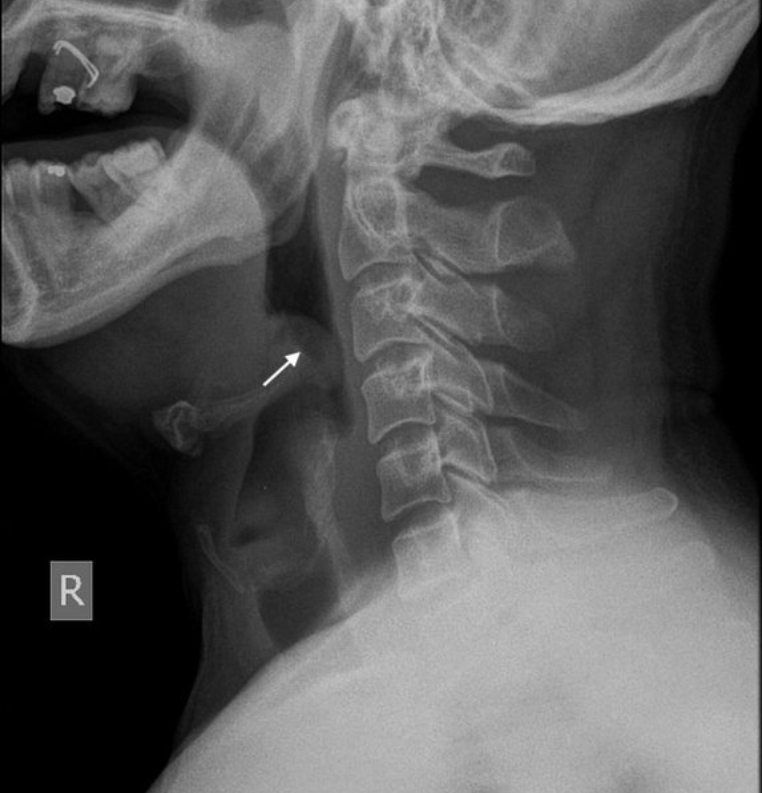

_____ sign on the x-ray is suggestive of acute epiglottitis.